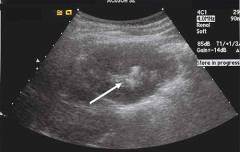

Ультразвуковое исследование (УЗИ) — высокоинформативный метод неинвазивной диагностики, основанный на использовании ультразвуковых волн. Эти волны проникают в ткани организма и отражаются от плотных структур. Отраженные волны регистрируются датчиком, который создает изображение, позволяющее оценить состояние органа.

УЗИ показано во всех случаях почечной колики, так как позволяет визуализировать изменения в почках и увидеть камни, которые не видны на рентгене.

При почечной колике ультразвук позволяет выявить следующие изменения:

- расширение чашечно-лоханочной системы;

- увеличение размера почки более чем на 20 мм по сравнению с другой почкой;

- плотные образования в лоханках, мочеточниках (камни);

- изменения структуры почки;

- отек почечной ткани;

- гнойные очаги в почке;

- изменение гемодинамики в почечных сосудах.

Ультразвуковое исследование (УЗИ) — это неинвазивный метод диагностики, использующий ультразвуковые волны. Эти волны проникают в ткани и отражаются от плотных структур или границ с различной акустической плотностью. Датчик фиксирует отраженные волны, измеряя их скорость и амплитуду, что позволяет формировать изображение для оценки состояния органа.

УЗИ показано при почечной колике, так как позволяет визуализировать изменения в почках и выявить камни, которые могут быть не видны на рентгене.

При почечной колике ультразвук позволяет выявить:

- плотные образования в лоханках и мочеточниках (камни);

- изменения структуры почки (предшествующие патологии);

- изменения гемодинамики в почечных сосудах.